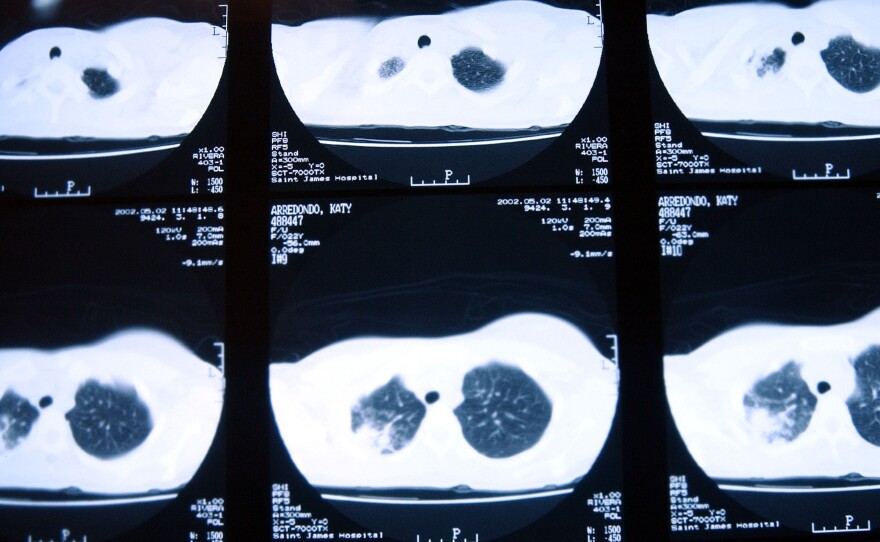

CT scans of a patient with tuberculosis, taken in November 2002 in New Jersey, show damage to the lungs.

Because of incorrect information from Getty Images, a previous photo caption misidentified a CT scan image as an X-ray.